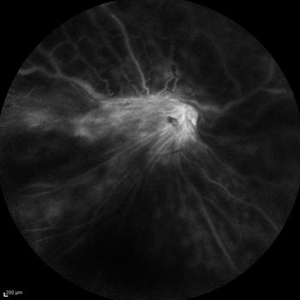

Idiopathic Retinitis, Vasculitis, Aneurysms, and Neuroretinitis (IRVAN) Idiopathic Retinitis, Vasculitis, Aneurysms, and Neuroretinitis (IRVAN)Nov 13 2013 by Hamid Ahmadieh, MD Wide -field late phase FA image of the right eye of a 35-year-old woman with idiopathic retinitis, vasculitis, aneurysms, and neuroretinitis (IRVAN). Photographer: Solmaz Shahmohammad , Negah Eye Center , Tehran Imaging device: Heidelberg Spectralis Condition/keywords: aneurysm, neuroretinitis, retinal vasculitis, retinitis

Idiopathic Retinitis, Vasculitis, Aneurysms, and Neuroretinitis (IRVAN) Idiopathic Retinitis, Vasculitis, Aneurysms, and Neuroretinitis (IRVAN)Nov 13 2013 by Hamid Ahmadieh, MD Late venous phase FA image of the right eye of a 35-year-old woman with idiopathic retinitis, vasculitis, aneurysms, and neuroretinitis (IRVAN). Photographer: Solmaz Shahmohammad , Negah Eye Center , Tehran Imaging device: Heidelberg Spectralis Condition/keywords: aneurysm, neuroretinitis, retinal vasculitis, retinitis

Idiopathic Retinitis, Vasculitis, Aneurysms, and Neuroretinitis (IRVAN) Idiopathic Retinitis, Vasculitis, Aneurysms, and Neuroretinitis (IRVAN)Nov 13 2013 by Hamid Ahmadieh, MD Mid-arteriovenous phase FA image of the right eye of a 35-year-old woman with idiopathic retinitis, vasculitis, aneurysms, and neuroretinitis (IRVAN). Photographer: Solmaz Shahmohammad , Negah Eye Center , Tehran Imaging device: Heidelberg Spectralis Condition/keywords: aneurysm, neuroretinitis, retinal vasculitis, retinitis